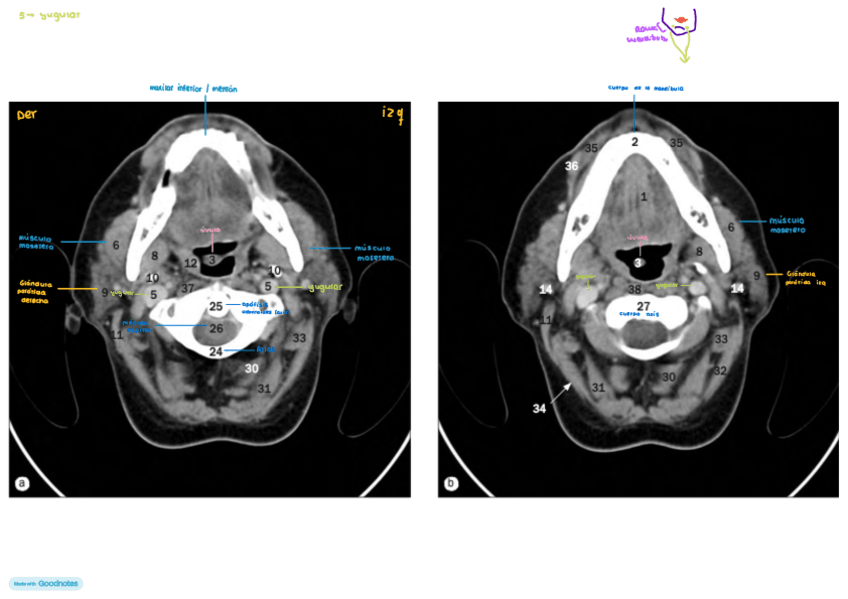

He publicado nuevos apuntes de Técnicas de Tomografía Computarizada y Ecografía: TC Y ECOGRAFÍA

IMAGENES-AXIALES-DE-CUELLO-con-anatomia.pdf